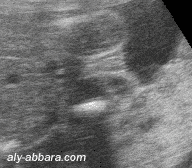

Organes génitaux externes féminins chez un fœtus de 22 SA

Cette image met en évidence l'aspect échographique du jet urinaire lors de la miction